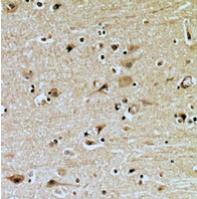

图片:

Immunohistochemical analysis of ZNRF2 staining in human brain formalin fixed paraffin embedded tissue section. The section was pre-treated using heat mediated antigen retrieval with sodium citrate buffer (pH 6.0). The section was then incubated with the antibody at room temperature and detected using an HRP conjugated compact polymer system. DAB was used as the chromogen. The section was then counterstained with haematoxylin and mounted with DPX.